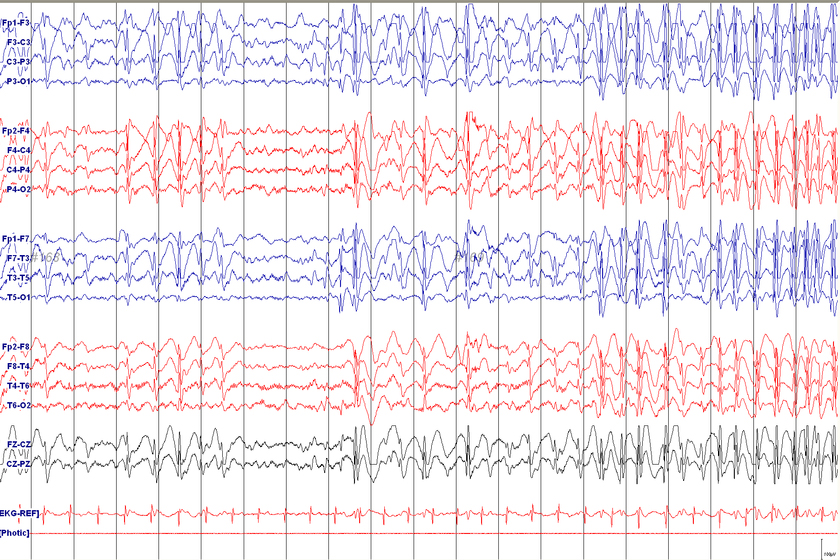

Tramite una valutazione clinica approfondita, un’anamnesi dettagliata del paziente e attraverso tecniche di imaging avanzate, come l’Elettroencefalogramma (EEG) e la Risonanza Magnetica (RMN).

- Un Elettroencefalogramma (EEG) che mostra anomalie specifiche.